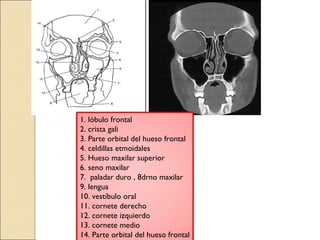

1. lóbulo frontal

2. crista gali

3. Parte orbital del hueso frontal

4. celdillas etmoidales

5. Hueso maxilar superior

6. seno maxilar

7. paladar duro , 8drno maxilar

9. lengua

10. vestíbulo oral

11. cornete derecho

12. cornete izquierdo

13. cornete medio

14. Parte orbital del hueso frontal